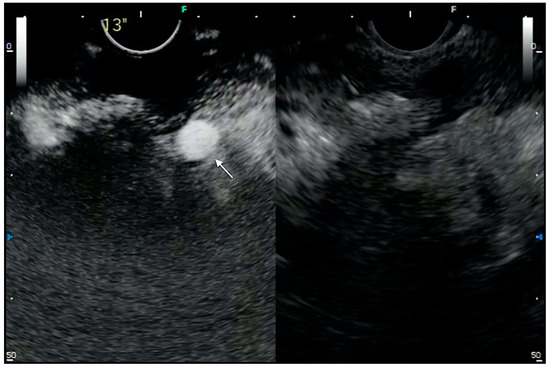

- Minaga, K.; Takenaka, M.; Omoto, S.; Miyata, T.; Kamata, K.; Yamao, K.; Imai, H.; Watanabe, T.; Kitano, M.; Kudo, M. A case of successful transluminal drainage of walled-off necrosis under contrast-enhanced harmonic endoscopic ultrasonography guidance. J. Med Ultrason. 2018, 45, 161–165. [Google Scholar] [CrossRef]